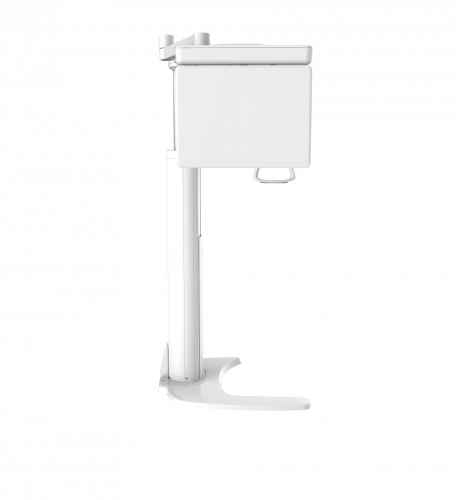

| TYPE | TOP VIEW | FRONT VIEW |

|---|---|---|

|

PaX-i (Pano) |

|

|

|

PaX-i SC (Pano/Scan Ceph) |

|

|